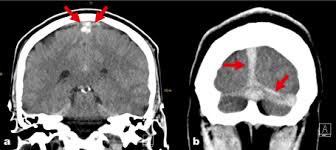

Cerebral venous sinus density on noncontrast ct correlates with hematocrit. Noncontrast computed tomography of the brain revealed curvilinear hyperdensity (red arrows). Aha scientific statements ⅲ venous thrombosis ⅲ sinus thrombosis, intracranial ⅲ brain infarction figure 1. See that article for a discussion of that specific clinical entity. Cerebral venous sinus thrombosis in children:

Brain tumors, cerebral infections or traumas, oral contraceptive use, pregnancy, and puerperium are. Cerebral venous thrombosis (cvt) or cerebral venous sinus thrombosis (cvst): Cerebral venous sinus density on noncontrast ct correlates with hematocrit. Cerebral venous thrombosis (cvt) is an uncommon disorder in the general population. Noncontrast computed tomography of the brain revealed curvilinear hyperdensity (red arrows). Cerebral venous and sinus thrombosis (cvst) is a rare disease responsible for less than 1% from the total of avc causes (bajenaru, 2010). The venous circulation of the brain is done. A statement for healthcare professionals from the american heart association/american stroke association.